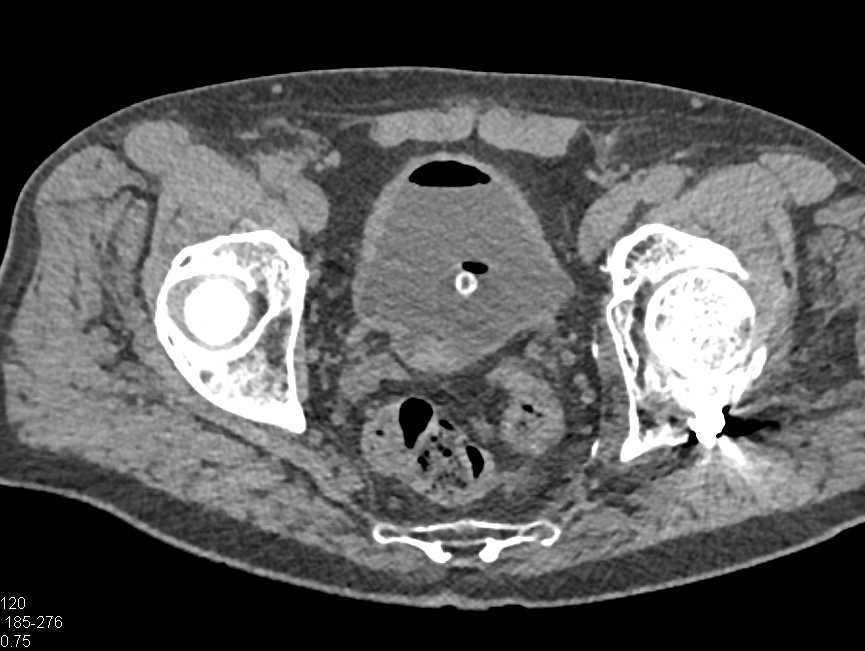

Minimal Thickening Ureter Without a Discrete Mass